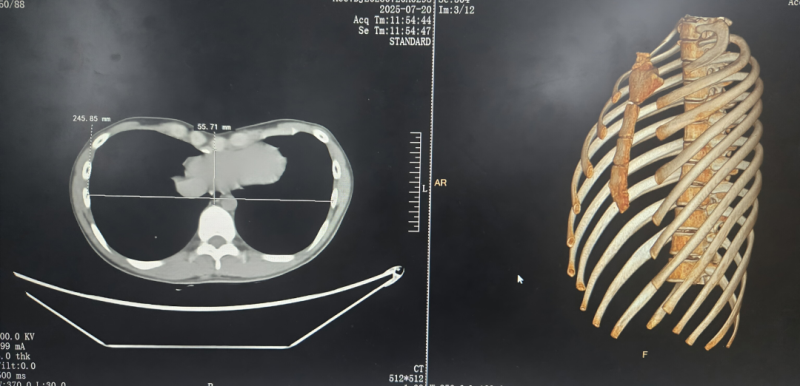

意识到问题的严重性后,李同学在家人的陪伴下来到漯河市中心医院心胸外科,寻求马广耀团队的帮助。经过详细的体格检查和胸部CT三维重建评估,确诊李同学为“重度漏斗胸”。影像学显示,其胸骨凹陷程度深,Haller指数提示畸形严重,心脏和肺部已受到一定程度的压迫。如不及时干预,不仅运动耐量会持续下降,呼吸困难等症状会加剧,心脏功能也可能进一步受损,同时伴随的心理健康问题也将愈发突出。